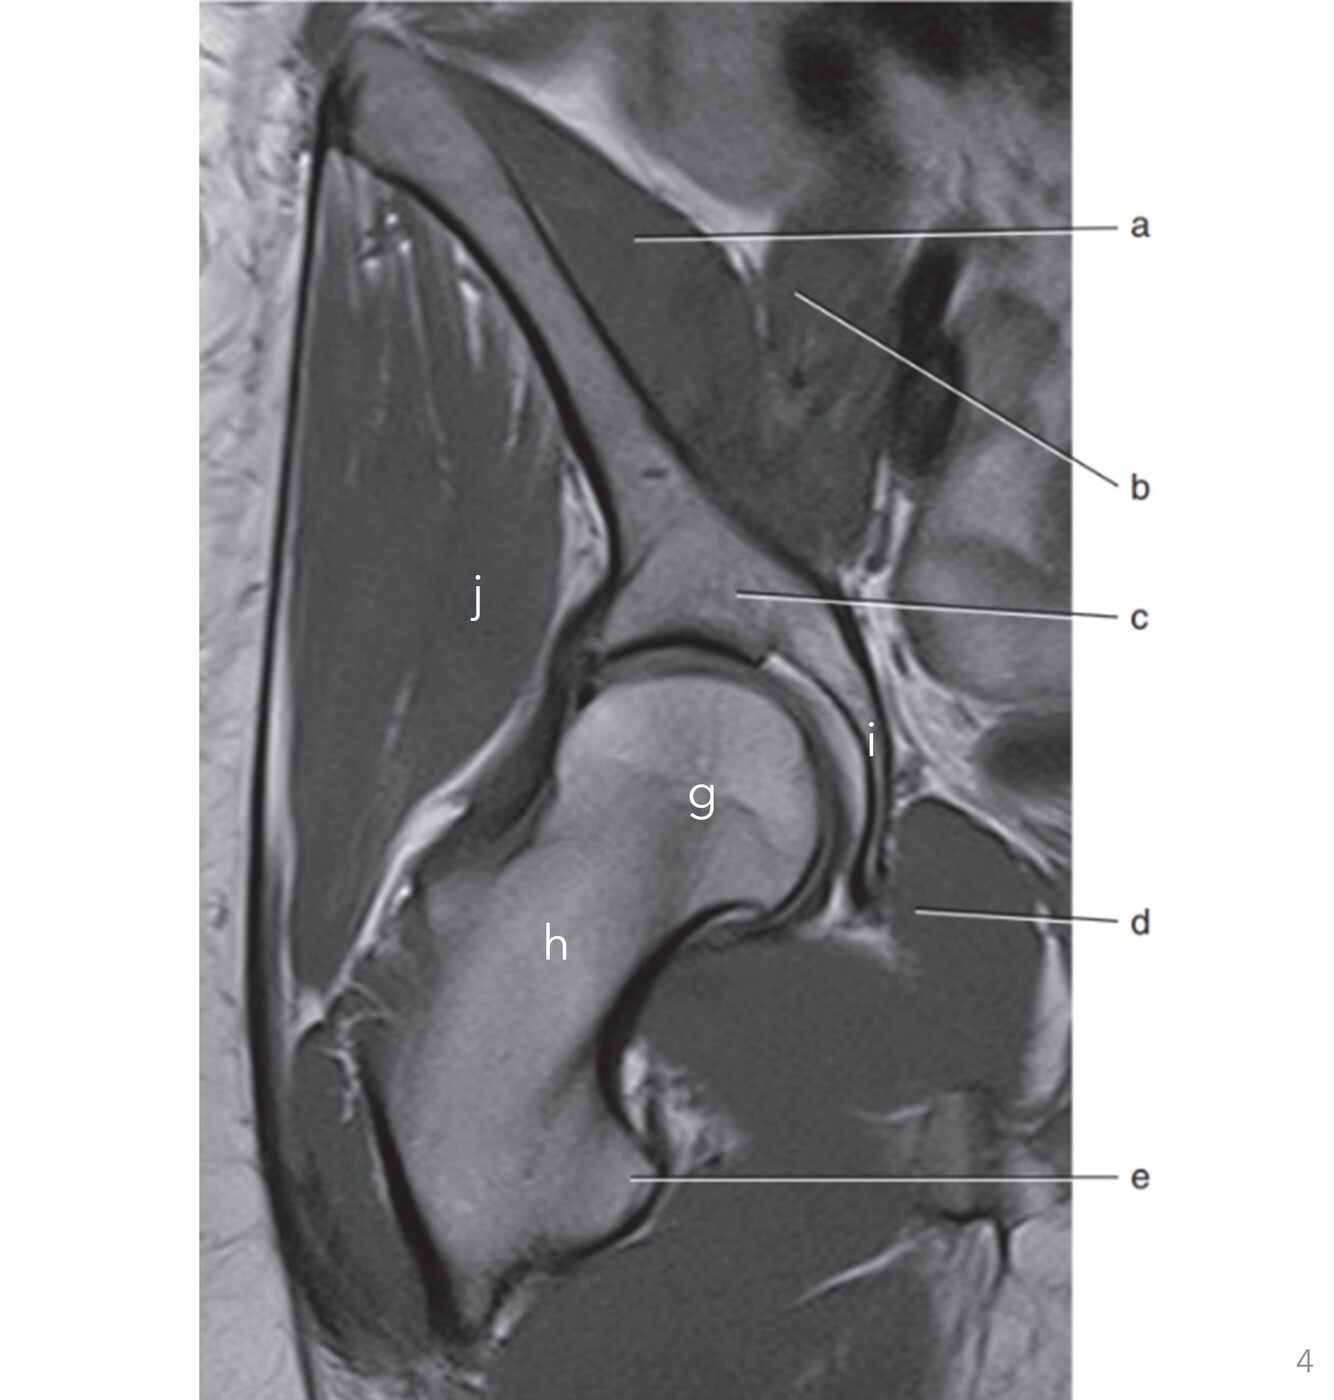

Label a,b,c,e,g,h,i,j

A

a=Rt iliacus

b=Rt psoas

c=Rt iliac body

e=Lesser trochanter (Rt femur)

g=Rt femoral head

h=Rt femoral neck

i=Rt ischium

j=Rt gluteus minimus